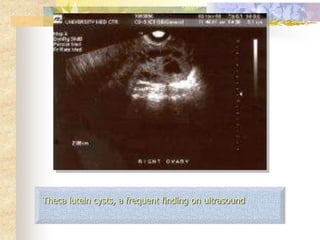

Complete mole

•Theca lutein cysts are frequent

findings on ultrasound

Theca lutein cysts, a frequent finding on ultrasound

 Theca-lutein cysts:

 Clinically evident theca lutein cysts (usually >5–6 cm) are

 They usually correlate with marked elevation of serum hCG